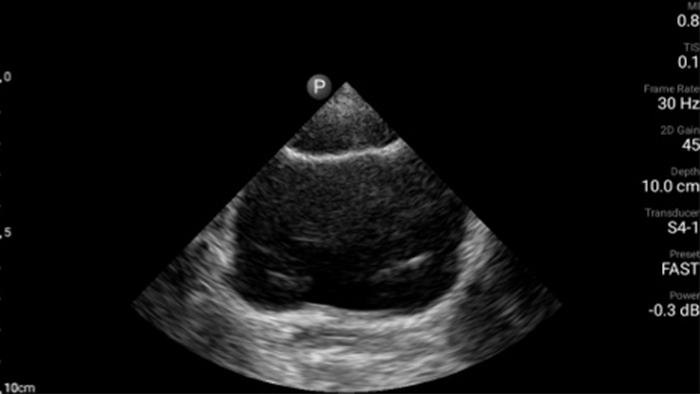

Act faster to protect their heart

When seconds count, portable ultrasound can make the difference. Lumify can provide the high-definition imagery you need whenever and wherever you need it.